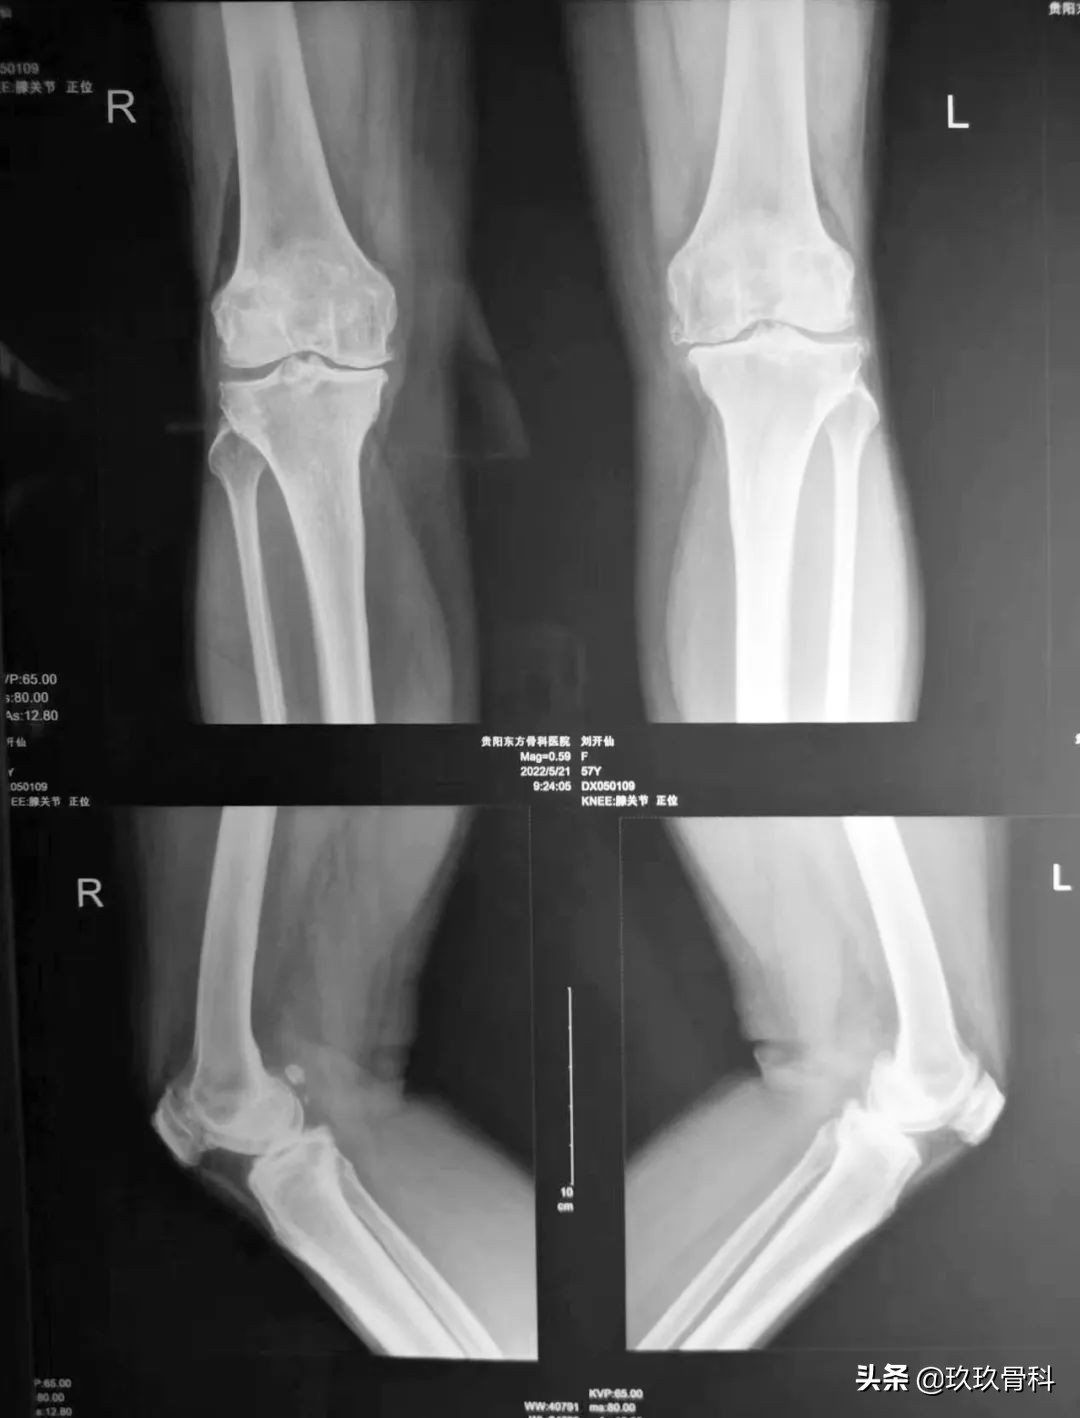

辅助检查: 双膝关节正侧位示:双膝关节退行性关节炎。

术前影像